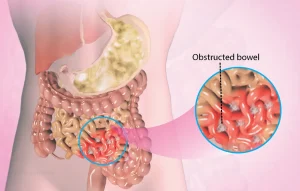

انسداد روده چیست و چرا میتواند کشنده باشد؟

انسداد روده، که در پزشکی به آن ایلئوس گفته میشود، وضعیتی موقت است که در آن رودهها قادر به عبور غذا و مواد زائد از بدن نیستند. رودهها لولههای طولانی و پیچخوردهای در داخل شکم هستند که معده را به مقعد متصل میکنند و به دو بخش اصلی تقسیم میشوند: روده کوچک و روده بزرگ.

روده کوچک وظیفه تجزیه و جذب مواد مغذی غذا را بر عهده دارد، در حالی که روده بزرگ با جذب آب و حرکات موجمانند، مواد هضم شده و زائد را به سمت مقعد هدایت میکند تا دفع شوند. ایلئوس زمانی رخ میدهد که این حرکات موجی موقتی متوقف شوند و معمولاً بین یک تا سه روز ادامه پیدا میکند.

این اختلال میتواند ناشی از عوامل مختلف و شرایط زمینهای باشد که باعث انسداد روده میشوند. انسداد میتواند بخشی از روده را درگیر کند (انسداد جزئی) یا کل طول روده تحت تأثیر قرار گیرد، که شدت علائم و ضرورت اقدامات درمانی را تعیین میکند.